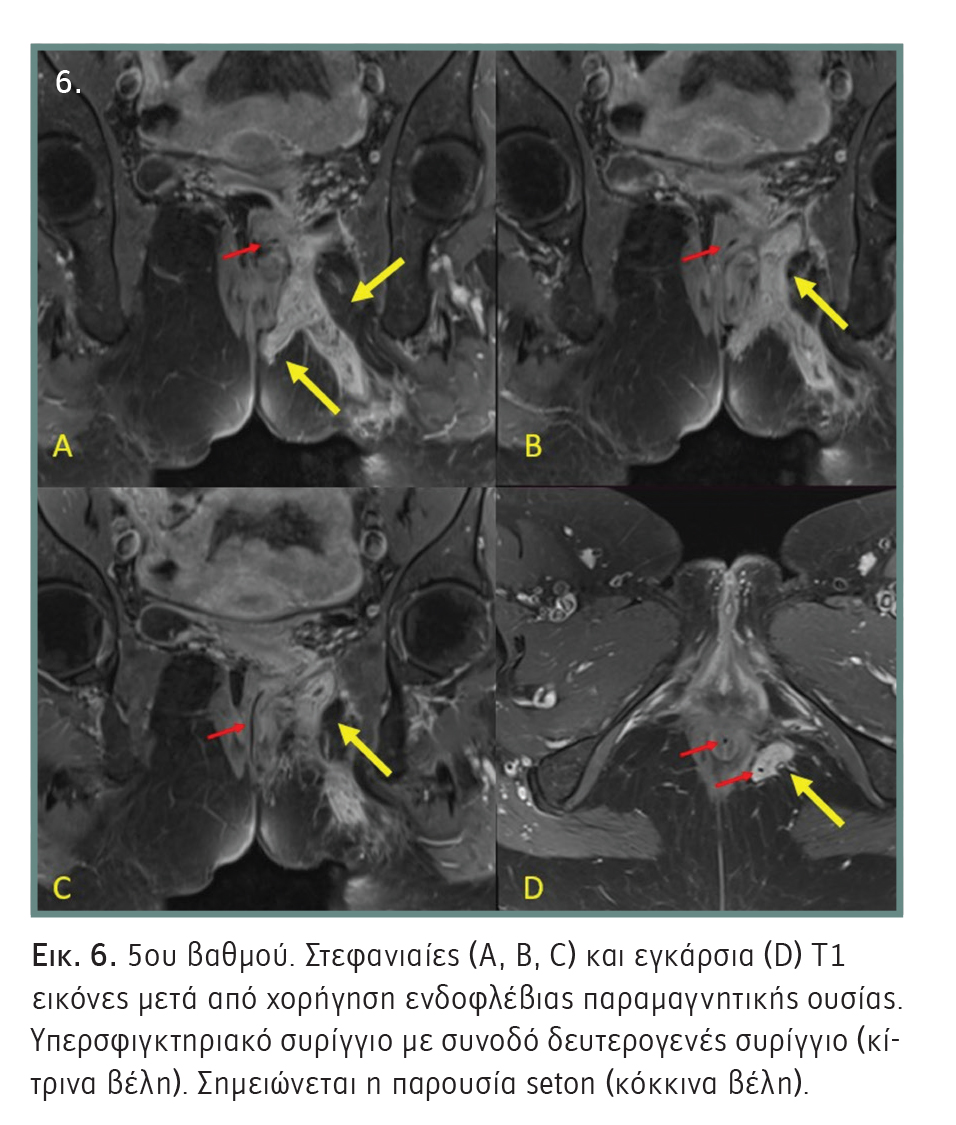

- 5ου βαθμού: Υπερανελκτήριο και διανελκτήριο συρίγγιο. Περιεδρικό συρίγγιο, το οποίο εκτείνεται πάνω από το επίπεδο εισόδου του ανελκτήρα μυός. Το υπερανελκτήριο συρίγγιο είναι παρόμοιο με το υπερσφιγκτηριακό και το διανελκτήριο με το εξωσφιγκτηριακό στην ταξινόμηση κατά Parks (Εικόνα 6).